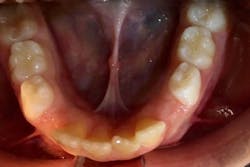

A good time to see where the lingual frenum attaches is when you examine the floor of the mouth. Does it attach into the floor of the mouth as it should? Or do you see it attaching to the alveolar ridge? When this attachment is present, it often presents as an “Eiffel tower” appearance (figure 1). This appearance may be indicative of a posterior lingual restriction. Further functional evaluation is warranted by an orofacial myologist.